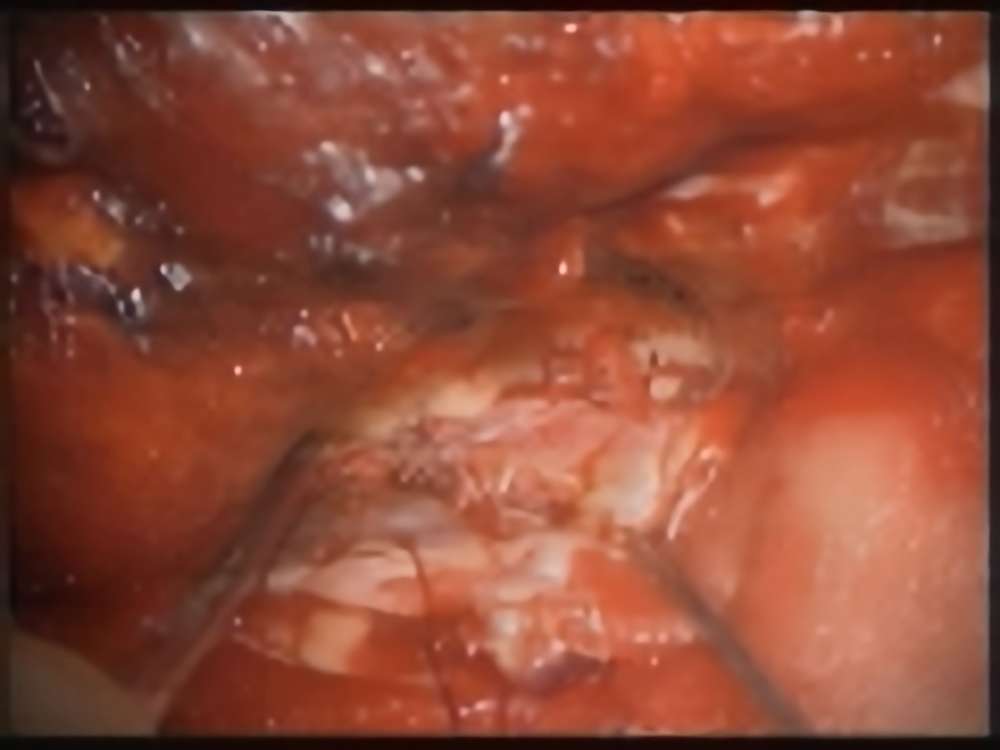

術中写真

摘出 前

摘出 中

摘出 後